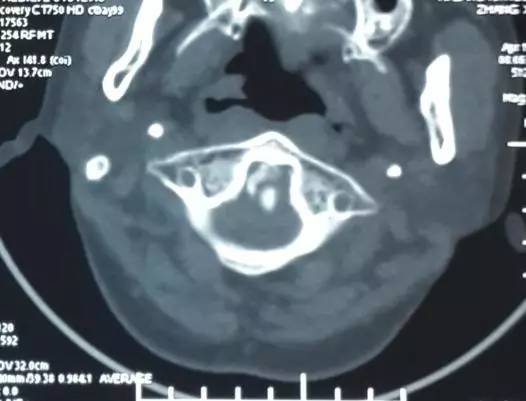

3影像学检查

手术前前屈位X光片寰枢椎脱位(寰齿前间隙7mm)。寰枢椎三维CT见寰枕融合,颅底陷入(齿状突位于钱氏线上14.2mm),右侧枢椎椎弓根发育狭小(小于2mm),磁共振显示小脑扁桃体下疝、颈髓损伤伴椎管狭窄。

4术前片子